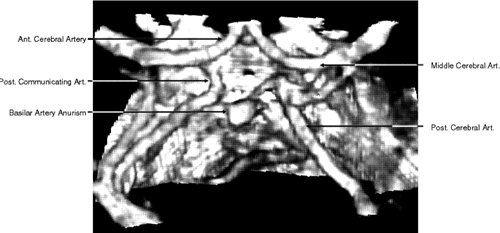

CTA of the intracranial vessels is an excellent tool for detecting cerebral aneurysm in patients with subarachnoid hemorrhage (Fig. 6). Compared with a standard cranial CT, it requires only a few more minutes to obtain detailed information about intracranial angiography. CTA obtained with multislice CT is a relatively new technology with promising implementations, but at present the clinical usefulness of multislice CT and CTA in neuroimaging is yet to be determined.

Fig. 6. Three-dimensional computed tomography angiography of the circle of Willis showing an aneurysm of the basilar artery.

With 2D TOF, multiple thin imaging slices are acquired with a flow-compensated gradient-echo sequence. Slice thickness is limited to 1.5 mm. These images can then be combined by using a technique of reconstruction such as maximum intensity projection (MIP) to obtain a 3D image of the vessels analogous to conventional angiography (Fig. 11). The 2D TOF MRA technique is robust and relatively fast; it may be adequate for screening, but it is less accurate for gauging the degree of stenoses.

Fig. 11. Two-dimensional time-of-flight magnetic resonance angiography of the circle of Willis (superior view).